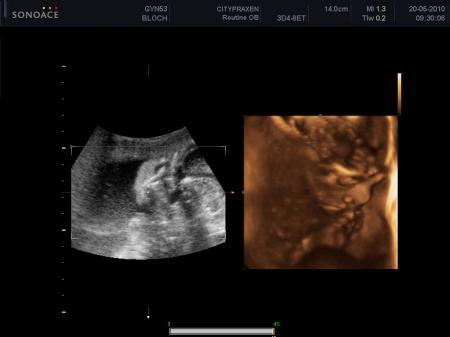

und ich möchte euch gern zwei Bilder von unserem bezaubernen Sohn Leandro zeigen! Er ist so süss und hat auch schön brav mit gemacht! Und ein Daumen nuckler war er heute!

Bild zu Heute 3D/4D gehabt - Forum für September - Mamis